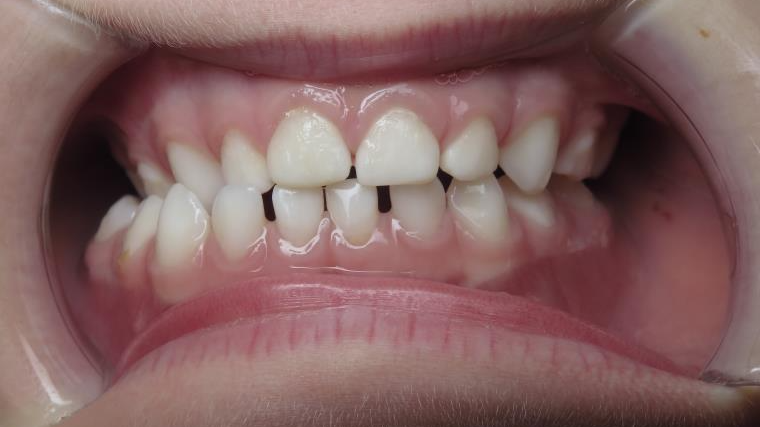

inversion des dents postérieur coté droit